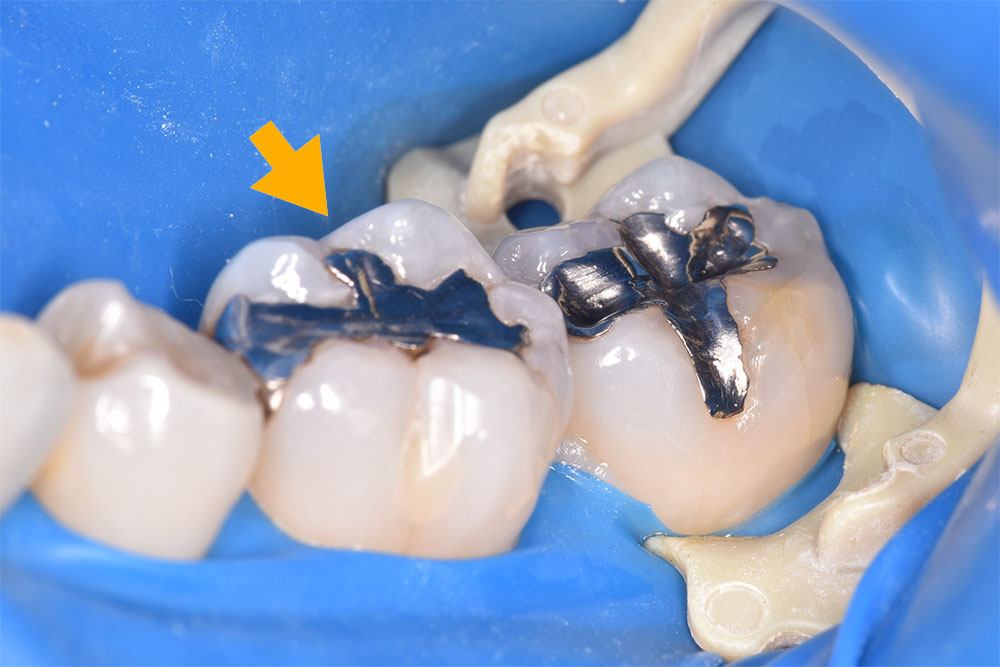

セラミックインレー治療のメインはセラミックスです。ダイレクトボンド治療との違いは、適用症例が異なります。セラミックインレー治療はダイレクトボンド治療と比べて、治療をする歯の範囲が大きくなります。今回の症例のように隣の歯に及ぶ銀歯での治療をされている場合、強度の面でセラミックインレー治療を適用します。( 黄色い矢印 )

セラミックインレーは治療回数は2回です。治療の1回目にセラミックスインレーの型取りを行います。そして2回目にセラミックインレーを接着剤を用いて、歯に装着します。治療の期間はおおよそ3週間です。

セラミックインレーを歯に装着する際も、ダイレクトボンドと同様にラバーダム防湿を行います。やはり、ラバーダム防湿をしないとセラミックインレーは強固に歯にくっついてくれません。セラミックインレー治療がより永くお使いいただけるように当院ではラバーダム防湿を必須で行っております。